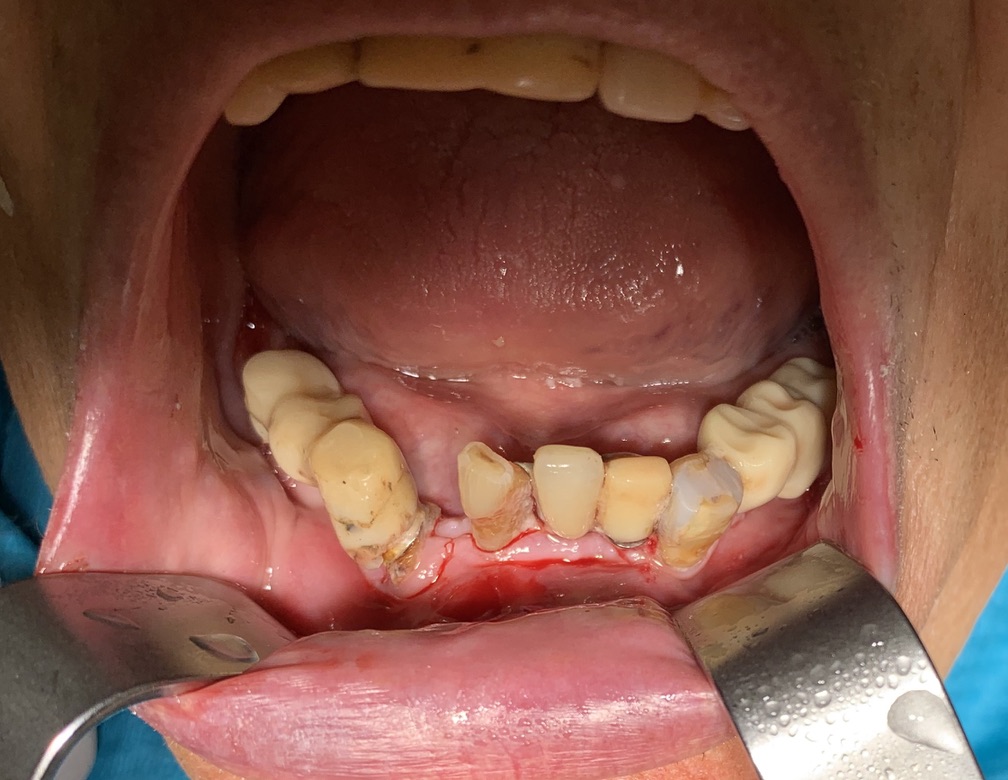

1 - AN INCISIVE CASE

Fracture of lower incisor element 31 and implant rehabilitation